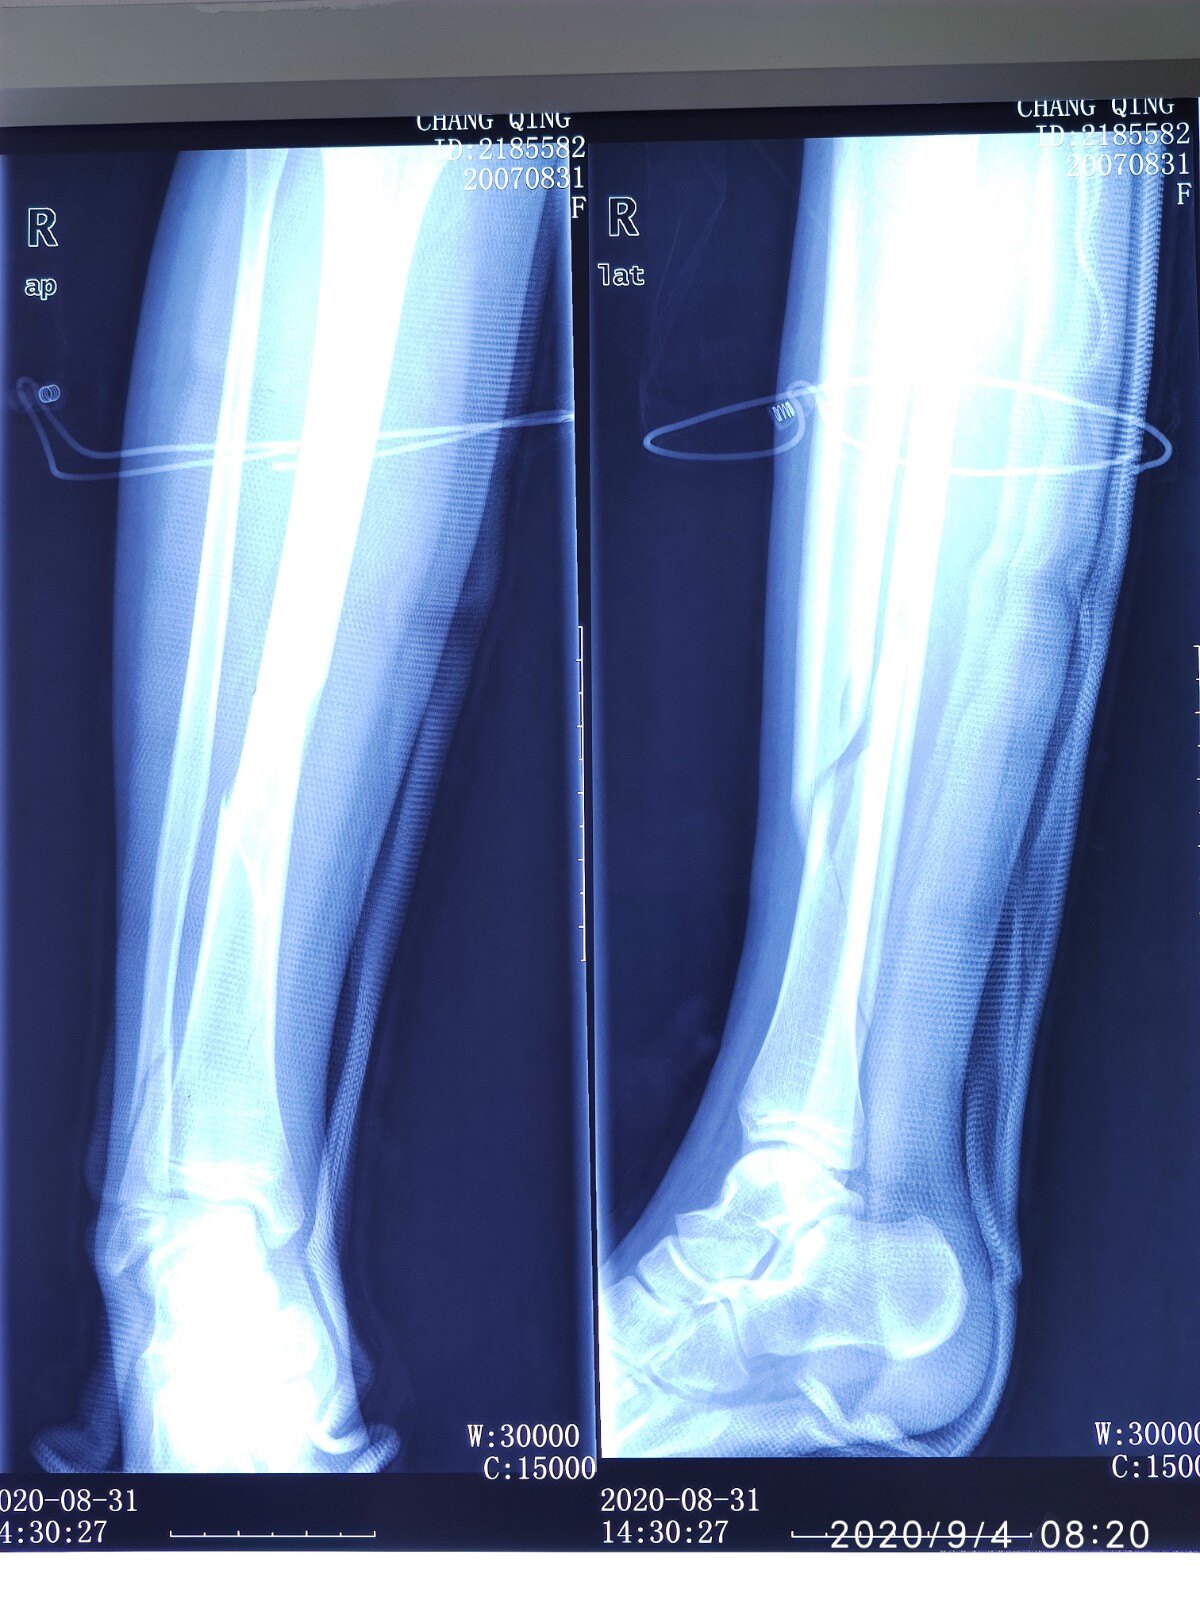

一般原則上除非是非常靠近上端 ( 脛骨平台骨折 ) 或是非常遠端 ( 近踝關節骨折 ),否則絕大多數的脛骨骨折案例,多是以骨髓內釘做為手術中固定物的首選。骨折を認めた(図1).ct像では両側ともに脛骨粗面部 の骨折を認め,右は骨幹部内側に向かう骨折線,左は骨幹 部外側から後方に向かう骨折線を伴っており,両側ともに sh2型の骨折であった.mriではct像で認めた骨折部 にt1・t2強調像ともに線状の低信号を下腿骨幹部骨折を受傷した10歳代の女性である。骨折 型はAO分類A3型であった(図1)。受傷当日に鋼線 牽引が施行され,受傷後4日目に髄内釘を用いた骨接合 術が施行された(図2)。手術は,脛骨粗面から膝蓋骨 下極に向かって約3 cmの皮切が置かれた。

整形外科と災害外科 60(4), 6176, ;文献「脛骨骨幹部骨折に対するlateral parapatellar approachによる髄内釘固定」の詳細情報です。JGLOBAL 科学技術総合リンクセンターは研究者、文献、特許などの情報をつなぐことで、異分野の知や意外な発見などを支援する新しいサービスです。またJST内外の良質なコンテンツへ案内いたします。脛骨骨幹部骨折をエンダー釘で固定することで脛骨を 安定させた.脛骨プラトー骨折に対しては関節面を整 復した後,外側ロッキングプレートで固定した(図 2). 2 週免荷とし,術直後より膝関節可動域訓練を開始し

脛骨骨折部(図 5)は関節面から約 4 cm 近位に第 3 骨片を伴うらせん骨折(AO 43A3)を認め,近位の 腓骨骨幹部にも骨折を認めていた.手術は脛骨骨折に 対して観血的整復固定術(図 6)を行い,後療法は 4 週免荷で 8 週全荷重の方針でリハビリを開始した.術脛骨骨折的症状 一、症状 體征: 脛骨骨幹骨折 小腿 腫脹、疼痛,可有畸形和異常動度。 脛骨平台骨折 膝關節腫脹疼痛,活動障礙,因系關節內骨折均有關節內積血。 二、檢查: x 線片檢查有助於骨折和骨折類型的診斷。 三、診斷:脛骨骨幹部骨折について 脛骨骨幹部骨折は「脛骨骨端部を除く骨幹部の骨折」を指す。 開放骨折や転移の大きい骨折は、交通事故やスポーツ中の事故、圧挫損傷など高いエネルギー損傷で生じる。 転位が無く安定した骨折は、転倒などの低エネルギー損傷で生じる。 局所の腫脹・疼痛・変形は著明で、ときにはショック状態を呈することがある。 脛骨骨幹部骨折

ワイヤーは骨幹端部の骨を確実に固定できるため、骨幹端部や関節内骨折への適用が可能です。 不安定型の脛骨プラトー骨 折では1つのリングに4本のワイヤー、脛骨遠位の骨幹端部骨折では3本のワイヤーを用いて十分な固定性が得られます 1,2) 。江頭 秀一,田口 学,高橋 知幹,林田 洋一,高井 聖子,高井 浩和,中島 英親; POINT 下腿骨骨折(脛骨骨折、腓骨骨折)とは すねの骨は脛骨と腓骨の2本からなりますが、下腿骨骨折はそのうち一方または両方が骨折することで、交通事故やスポーツ、転倒が原因で起こることが多いです。 骨折した部分は腫れや痛み、内出血がみられます。 レントゲン検査やCT検査などの画像検査によって骨折の部位や程度が調べられます。 骨折の程度によっ